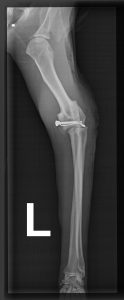

Nach vier Tagen war die Zeit der Ungewissheit für Luckis Besitzer endlich vorbei. Der Kater lebte, maunzte aber vor Schmerzen, nachdem er auf einmal wieder humpelnd im Garten aufgetaucht war. Vermutlich hatte das Tier einen Autounfall gehabt, denn im Röntgenbild erkannte der Tierarzt eine Ellbogenluxation. Versuche, das Gelenk wieder einzurenken, schlugen fehl. Zu alt war die Verletzung, die Schäden waren bereits zu groß, es drohte eine Amputation. Doch unserem Chefchirurg Dr. Klaus Zahn gelang das Kunststück, in einer diffizilen OP den Ellbogen mit einer Drahtzug-Gurtung wieder in der richtigen Position zu fixieren. Dadurch besteht Hoffnung, dass der Kater (im Foto mit Stationsärztin Lara Ißl) in ein paar Wochen sein Bein wieder voll belasten kann. Sofern Tier und Halter einige Regeln befolgen: sechs Wochen Zimmerhaltung, keine Sprünge, viel Physiotherapie. Um die Genesung ihres Lieblings zu unterstützen, haben die Halter daher eine geplante Flugreise storniert und freuen sich, dass Lucki bereits von Tag zu Tag besser läuft.